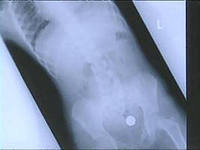

Камский детский медицинский центр раскрыл тревожную статистику - его маленькие пациенты проглотили в прошлом году аж 95 предметов. Чаще всего это были болтики, магниты, батарейки, монеты и мелкие детали игрушек. Самые частые герои таких историй - жители Набережных Челнов, которым еще не исполнилось трех лет. В этом случае врачи наблюдают за пациентом в хирургическом отделении. Иногда все обходится - проглоченное выходит "самостоятельно".

Но иногда приходится делать операции. В КДМЦ были случаи, когда хирург извлекал из кишечника малыша иглу.